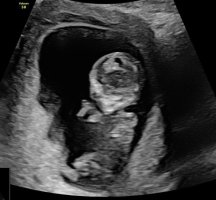

Siste bilde så kan se se ut som en guttHar disse, men tror ikke nub viser her

Ser lårbenet og da kan man ikke se nun dessverreMulig å se noe her? 14+0 <3